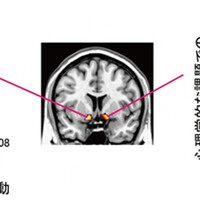

2014年8月6日 阿部修士 こころの未来研究センター特定准教授らの研究グループは、機能的磁気共鳴画像法と呼ばれる脳活動を間接的に測定する方法と、嘘をつく割合を測定する心理学的な課題を使って、正直さ・不正直さの個人差に関係する脳の仕組みについて解明しました。 本研究成果は、米国科学雑誌「Journal of Neuroscie…